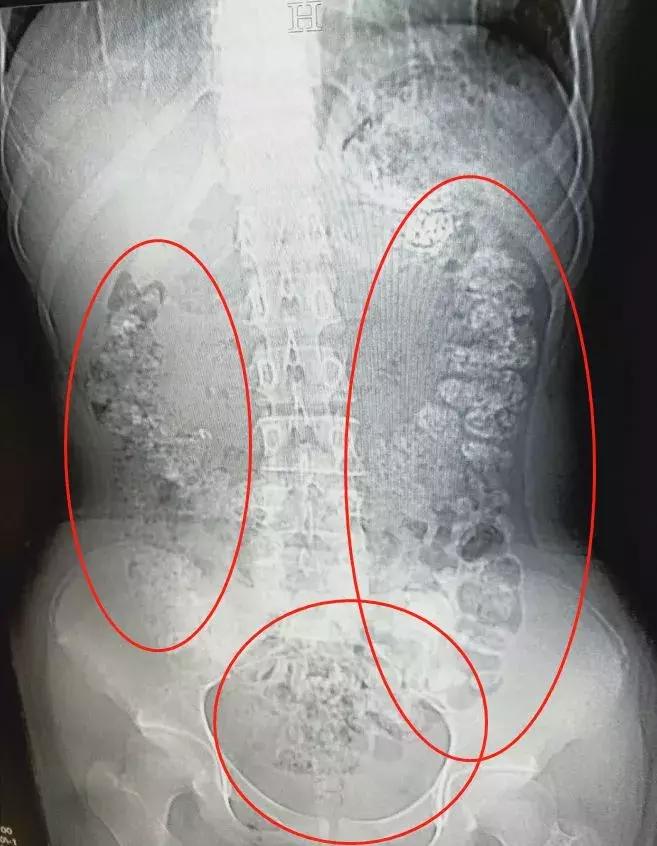

急诊科医生张楼炜对朱丽进行了初步检查,发现她肚子鼓鼓的,就让她去做了腹部CT,谁知道,拍出来的片子让张楼炜大吃一惊,患者胃部、横结肠、升结肠、降结肠、乙状结肠,一直到肛门,全是颗粒状阴影,足有百余颗。